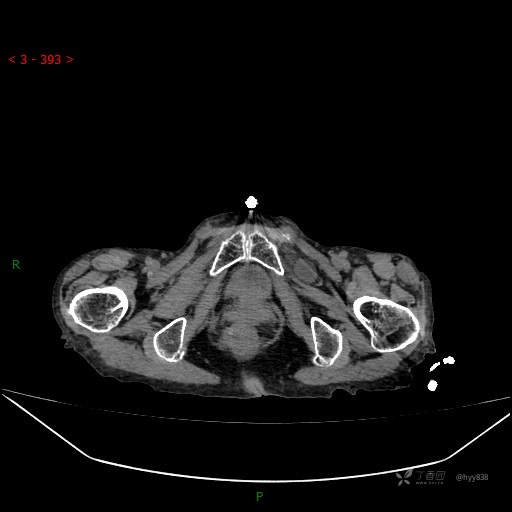

腹部CT平扫